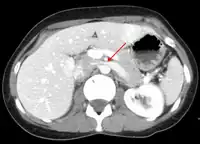

Thrombosis in the left renal vein associated with dilation- Summary video explaining signs and symptoms as well as etiology of nutcracker syndrome